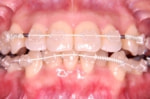

審美ブラケット

メリット

* 目立ちにくい

* 歯みがきしやすい

*ホワイトワイヤーとの組み合わせで更に目立ちにくくなりました。

デメリット

* 装置についた汚れがわかりにくい

* 若干コストが高くなります

※基本的に、金属・セラミックどちらのタイプで治療を行っても期間や効果は変わりません。